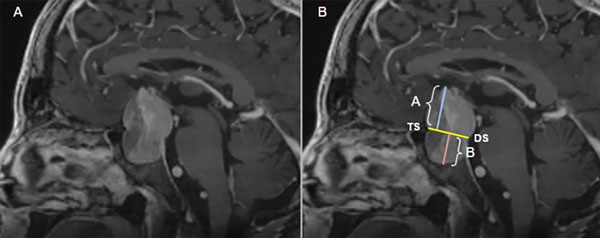

Se estableció un parámetro radiológico para valorar la extensión supraselar e infraselar, trazando una línea en el plano sagital desde el tuberculum selar al dorso selar (plano TS-DS), replicando la extensión del diafragma selar. A partir de este plano imaginario se traza una línea con una angulación de 90° tomando como punto de referencia el cenit tumoral. De esta forma, se cuantifica el máximo grado de extensión cefálica tumoral. Asimismo, se ideó una clasificación para subdividir en grupos según la distancia de extensión tumoral cefálica, estos son los grupos A (extensión 1-5 mm en sentido cefálico desde el plano TS-DS), el B (extensión de 6-10 mm), el C (extensión de 11-15 mm), y el subgrupo D (para aquellas lesiones que presentan una extensión superior a los 15 mm). A partir del plano TS-DS, además, se planteó trazar un plano con la misma angulación en sentido caudal al “nadir” tumoral, y así se cuantifica el máximo grado de extensión caudal. De estas medidas se obtiene el “coeficiente selar" (valor obtenido de la relación entre la extensión tumoral supra y subyacente al plano “tuberculum selar - dorso selar“ TS-DS) (Figura 4). Gracias a estos valores se logró obtener una medición cuantitativa y objetiva de la extensión tumoral en un plano cefalocaudal de forma simultánea, y así poder establecer un valor que determina si una lesión presenta mayor extensión supra o infraselar, con el fin de determinar el compromiso del diafragma selar y estimar el riesgo de desarrollo de fístula de LCR.

Figura 4. Resonancia magnética de encéfalo ponderada en una secuencia T1 con contraste (gadolinio) en un plano sagital. A) Imagen tumoral selar. B) Se han graficado, para la interpretación: el plano tuberculum selar – dorsal selar (TS-DS) y las variables de extensión tumoral suprayacente al plano TS-DS (A = 29.07 mm) y la extensión tumoral subyacente al plano TS-DS (B= 13.34 mm). Con la medición de estas variables se obtiene el “coeficiente selar” (CS= A/B).